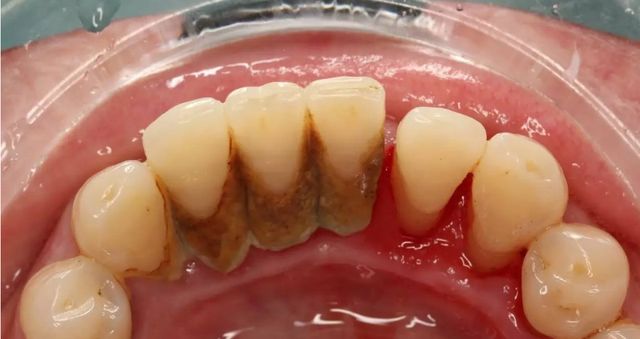

Toothbrushing is indeed the foundation of daily oral care, but its effectiveness is far from perfect . Even with diligent daily brushing, most people are unable to completely control the formation of dental plaque . Dental plaque is a biofilm composed of bacteria, food debris, and saliva that continuously reforms on the tooth surfaces . It particularly thrives in areas difficult to reach by toothbrushes, such as between the teeth (interproximal areas) and within the gingival sulcus .

Professional teeth cleaning, medically referred to as "supragingival scaling" , is the process of using specialized instruments to remove supragingival calculus (tartar), plaque, and stains from the teeth . Unlike daily brushing, professional cleaning can access and thoroughly clean areas that toothbrushes cannot effectively reach, such as the gumline and deep between the teeth, effectively removing established calculus and tenacious plaque deposits .

Thorough Removal of Plaque and Calculus: Addresses deep cleaning issues that brushing cannot handle, eliminating the primary cause of periodontal diseases .